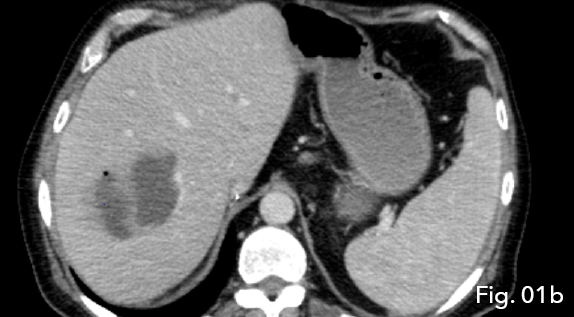

CT demonstrated intrahepatic blood flow via arterial collateralisation secondary to occlusion of the hepatic artery at the level of anastomosis proper as well as occlusion of the conduit vessel. A multiloculated, peripherally enhancing lesion with a low density centre and single gaseous loculation was seen in segments V and VIII of the liver. Due to the acute onset of clinical symptoms and new imaging findings, abscess formation secondary to ischemic liver disease was concluded (Fig 1a and 1b).

Figure 1b: Note the multiloculated/ spectated nature of the low density lesion (star) with gaseous loculation seen in the non-gravity dependent portion of the abscess (arrow).